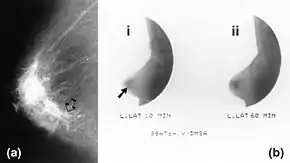

![]() Mammography (left) and DMSA scintimammography (right) images of 4.5cm breast carcinoma | |